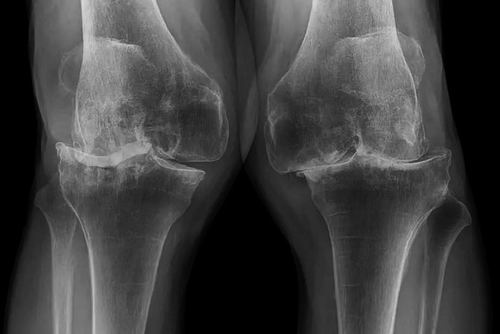

随着年龄的增长,骨关节炎是膝关节疼痛的常见原因,它包括软骨的磨损和撕裂。软骨是覆盖在骨头末端的一层类似橡胶的物质,能够防止骨头摩擦。